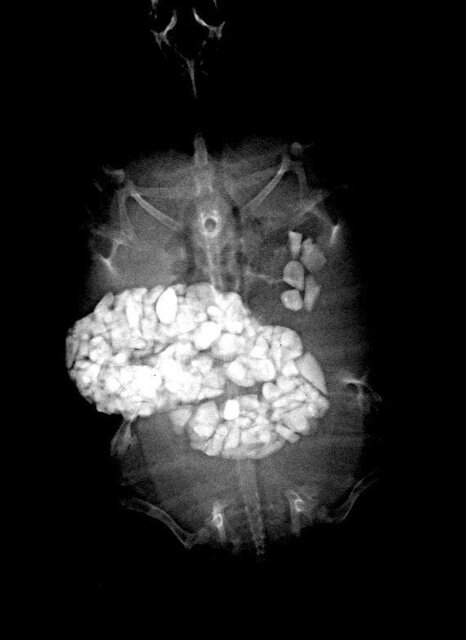

Не ведаю, как обстоят дела у кур и динозавров, но у черепах это может выглядеть примерно так:

В природе они не живут, а выживают, причем выживают самые генетически одаренные особи: быстрые, активные, агрессивные, прожорливые, неприхотливые, хитрожопые и сообразительные, а большая часть погибает еще в детстве - естественный отбор называется. Едят они в природе камни или нет, опять же не могу сказать наверняка, но если и съедают, то так же отлетают с закупоркой кишечника на радугу, после чего их оперативно съедают другие, поэтому диагностики и статистики по таким темам нет. Конкретно в условиях террариума наблюдается такое явление, как изменение пищевого (и не только) поведения, когда черепаха, будучи долгое время равнодушной к декору и оборудованию, в любой момент может начать кусать и глотать камни, ракушки, искусственное покрытие мостика, мелкий пластиковый декор, присоски и провода от фильтра и нагревателя и тд - результат на фото выше.